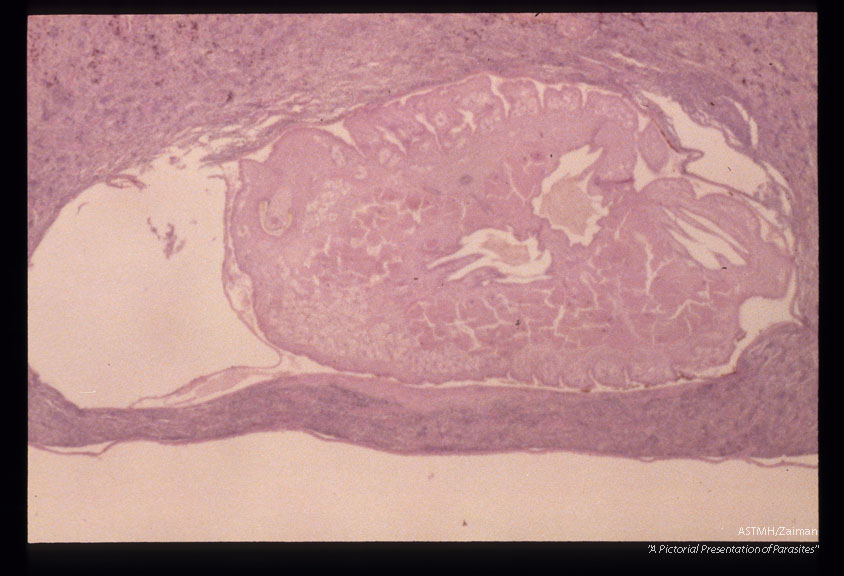

Nymphs in liver.

Armillifer armillatuy

Description: Nymphs in liver.